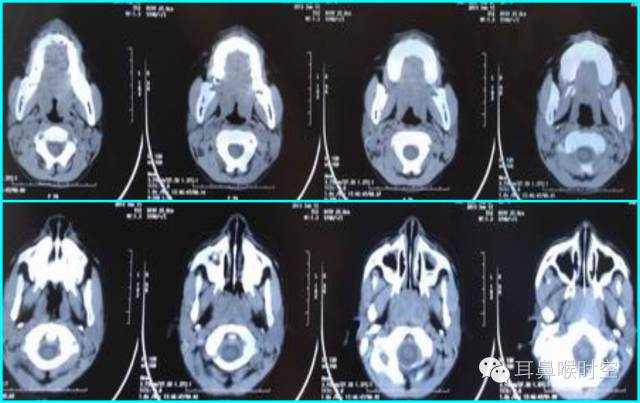

C T— computed tomography

咽部正常CT表现

(1)鼻咽腔层面:

(2)口咽腔层面

(3)喉咽腔层面:

CT检查扫描方法

①鼻咽部轴扫:常规OML (听眦线)

扫描体位:标准仰卧头颅正位

扫描参数:OML基线,层厚3mm/5mm,螺距1.0。

扫描范围:以侧位作为定位线,包括中耳乳突进行螺旋方式扫描

部分进行静脉增强扫描;

CT 观察与测量方法

①标准CT 轴位:主要观察12项结构

鼻咽腔的形态

腺样体大小与形态

咽隐窝

咽鼓管咽口

圆枕

鼻后孔的阻塞情况

翼内外板

翼内外肌

咽旁间隙

邻近骨质有无破坏

鼻旁窦

中耳乳突等。

标准CT 轴位像:

鼻咽气腔形态因层面不同而不同,其中,呈梯形(图3),长方形(图4)。

咽隐窝及咽鼓管咽口清晰或隐约可见,双侧对称,鼻后孔大部分畅通,咽旁间隙清晰,邻近骨质无破坏。